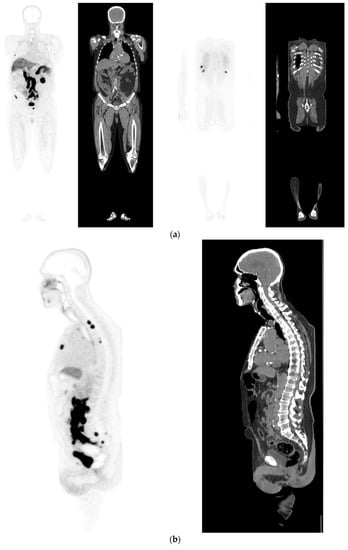

Figure 2.

Primary staging. 70 yr old M; PSA 42; Gleason 4 + 5 = 9; MR scan—PIRADS 6 at right apex; PIRADS 4 at left midzone. PSMA PET-CT: 68Ga-PSMA - 216 MBq; uptake 48 min; BMI = 30.5; Wt 83 Kg. (a): Coronal images—focal uptake midline apex anterior SUV = 26.1 with smaller focus SUV-5.4 right midzone; bulky disease in abdominal nodes; metastasis left humerus; left para-aortic node in thorax; bony metastasis left side of S1. (b,c): enlarged coronal and transaxial images of left common iliac/para-aortic nodal disease and uptake in apex of gland; transaxial images—node measures 14 mm SUV = 40.1; X-hairs show location. (d,e): enlarged coronal and transaxial images of right pelvic nodal that measures 1.4 mm SUV = 5.1; uptake in right midzone and apex as well as disease in left midzone of gland; X-hairs show location. (f,g): enlarged coronal images of para-aortic/para-oesophageal nodal disease in mediastinum; node measures 5.5 mm, SUV = 17.2; X-hairs show location.